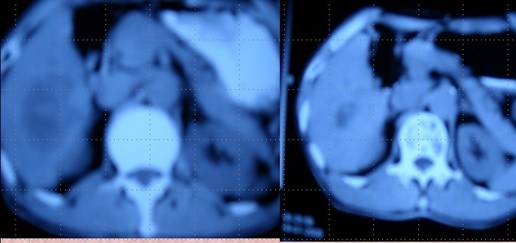

XX,男,67歲,退休工人,家住黑龍江雞西市。該患于20083月因肝左葉癌在哈爾濱醫(yī)科大學二院行肝左葉切除術(shù),術(shù)后三個月復查肝CTMRI示肝右葉轉(zhuǎn)移,遂于當?shù)氐V務(wù)局總醫(yī)院做了一次血管介入化療栓塞治療。三個月后復查再次出現(xiàn)肝右葉3個轉(zhuǎn)移灶,其中最大的直徑達5.5cm,又在雞西市中醫(yī)院腫瘤科做了一次射頻消融治療。當時只對最大的轉(zhuǎn)移灶進行了處理,小的沒做處理,患者從確診以來一直在積極求治,結(jié)果是一邊治療一邊轉(zhuǎn)移,最后一次治療結(jié)束后,家屬決定讓病人試一試中醫(yī)。于是該患者于200811月末開始到市中醫(yī)院腫瘤科求治與本人,經(jīng)采用“董氏調(diào)胃、強腎、止血、化巖治癌法”治療,患者服藥2個月后復查肝CT及彩超均未提示肝臟有另外兩個小轉(zhuǎn)移灶,而最大的轉(zhuǎn)移灶也明顯變小為2.5x3cm,繼續(xù)治療三個月復查肝CTMRI均提示射頻消融術(shù)后改變。之后多次復查均為肝左葉切除術(shù)后改變,肝右葉射頻消融術(shù)后改變。回訪至今患者一切如常,患者已無病生存3年。

肝癌病人楊XX采用“董氏治癌法”治療前后 CT對照變化